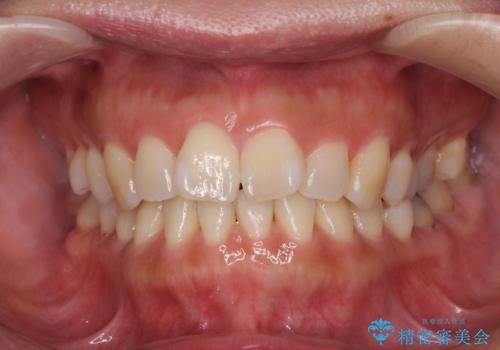

- 上下前歯の叢生を気にして来院された患者様です。

費用を抑え、期間もあまりかけずに治療をしたいとのことで、インビザライン・ライトを用いて矯正治療を行うこととしました。